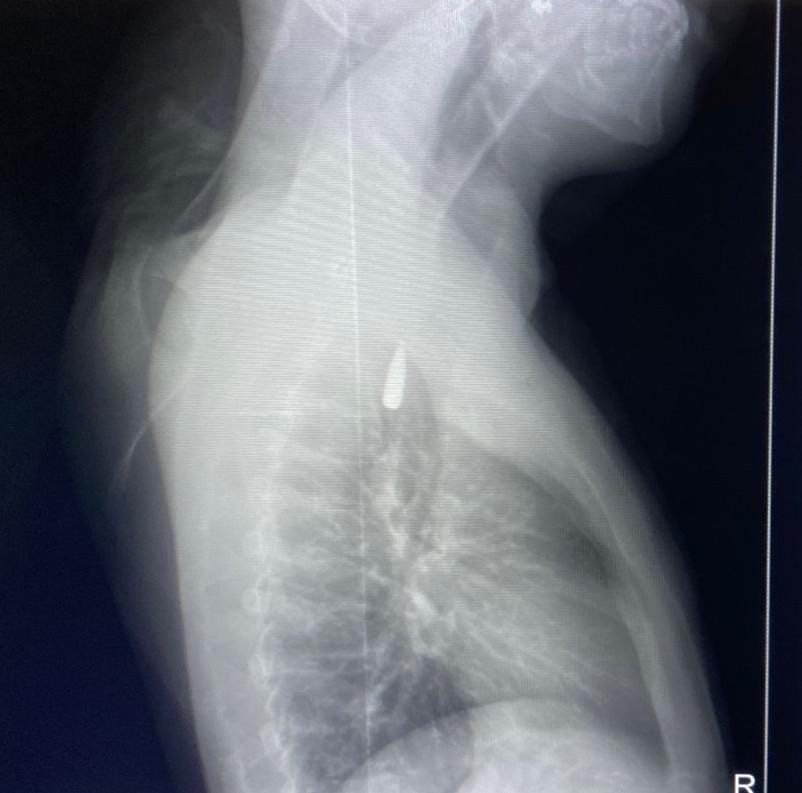

وأوضح الدكتور تامر عبد الله، عميد كلية الطب ورئيس مجلس إدارة المستشفيات الجامعية، أنه في يوم 21 أكتوبر 2025 تمكن فريق من أطباء قسم جراحة القلب والصدر والتخدير والمعاونين من إجراء جراحة دقيقة بالغة الخطورة لأحد المرضى المحجوزين من قطاع غزة، والذي كان قد تعرض لإصابة بطلق ناري في الرأس منذ فترة، استقر المقذوف على إثرها داخل تجويف القفص الصدري قرب الشريان الأورطي، وهو أكبر وأهم شرايين الجسم والمسؤول عن تغذية جميع الأعضاء الحيوية.

وأضاف أن الفريق الطبي، رغم دقة الحالة وتعقيدها، نجح في استخراج المقذوف بأمان بعد عملية جراحية نادرة استمرت عدة ساعات داخل المستشفى الجامعي الجديد، حيث خضع المريض بعدها للرعاية الطبية اللازمة، وحالته حاليًا مستقرة وتحت المتابعة الدقيقة من الفريق المختص.